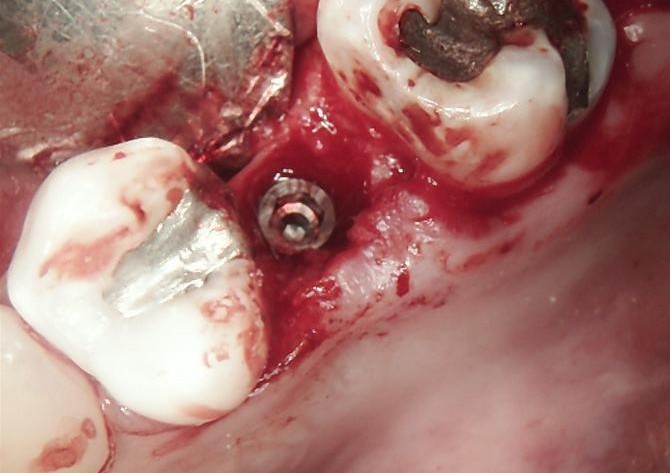

SURGERY

The failed implant was atraumatically removed, followed by thorough debridement of the surgical site.

Bone graft material was placed to restore adequate bone volume and support future implant placement.

A new implant was inserted in a prosthetically driven position, ensuring primary stability.

Surgical site was sutured to allow uneventful healing.